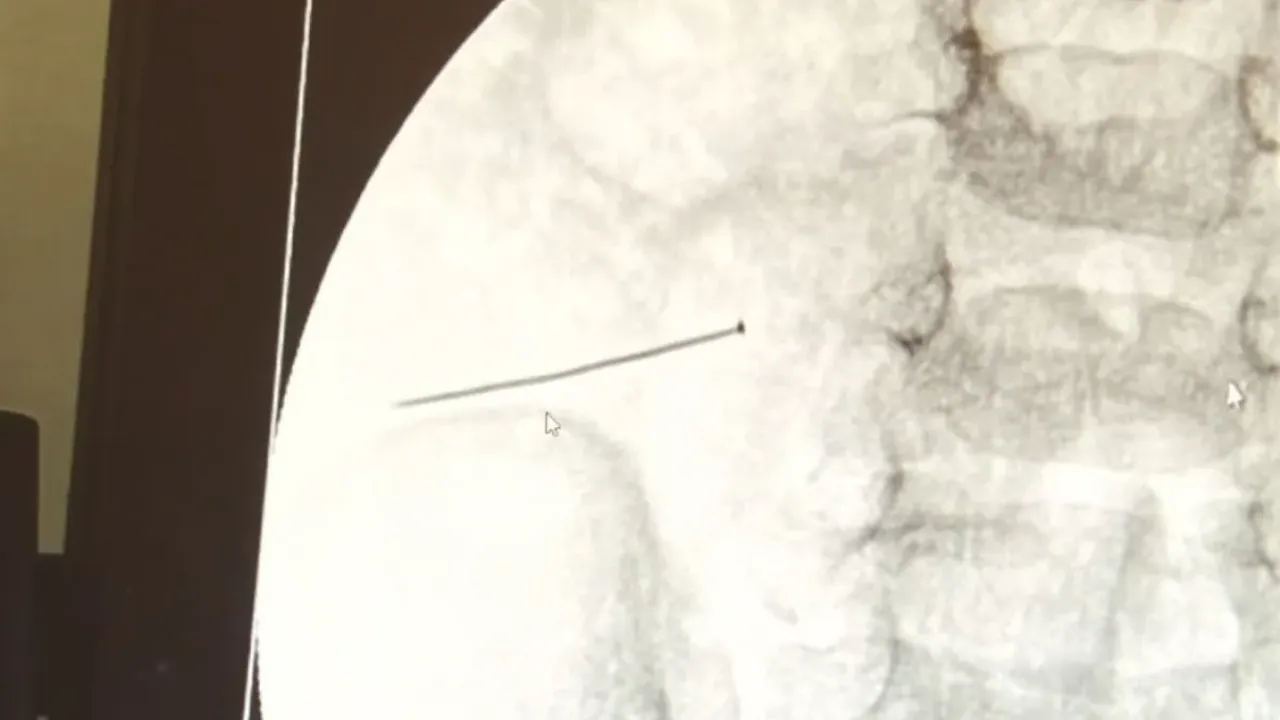

Burada yapılan tetkiklerde 2 yaşındaki çocuğun ince bağırsağında yaklaşık 3 santimlik toplu iğne olduğu ve bağırsağı deldiği belirlendi. Görüntülemeler sonrası 30 Ekim akşamı Çocuk Cerrahisi Kliniği Eğitim ve İdari Sorumlusu Doç. Dr. Sefa Sağ ve ekibi hemen ameliyata girdi.

Çocuklarda yabancı cisim yutulmasına yönelik konuşan ve hastasına ilişkin bilgi veren Doç. Dr. Sefa Sağ, "Soluk borusuna kaçması durumunda çocuğun Allah göstermesin ölümüyle veya ömür boyunca yatağa bağımlı kalmasıyla neticelenebilecek sonuçlar doğurabiliyor. Yutulması durumunda da gastrointestinal sistemin herhangi bir yerine takılmadığı müddetçe ekseriyâ yabancı cisimlerin dışarıya çıkmasını bekliyoruz. Yabancı cisim yutulmasını 2 grupta inceleyebiliriz. Sıvı ve katı cisimler olarak sıvı; evde kullanılan kimyasal temizlik malzemelerinin yutulması çok ciddi problemler oluşturabilmekte. Ağızda, yemek borusunda ve midede yanıklar meydana getirebilmekte. Uzun dönemde çocukların hayat kalitesini oldukça etkileyen sonuçlar doğurabilmekte. Katı cisimlerden de ekseriyâ kendiliğinden çıkmasını bekleriz ancak böyle delici, kesici aletlerin yutulmasında ise herhangi bir bağırsağın veya gastrointestinal sistemin bir parçasında delinmeler meydana getirebiliyor. Bu çocuğumuzda da aynen böyle bir hadise meydana gelmişti. Sanırım 1 gün önce ailenin yuttuğunu tahmin ettiği bir yabancı cisim; toplu iğne. Ertesi gün bağırsakta delinmeyle sonuçlanmış ve çocukta da ciddi semptomlar meydana getirmişti. Bu şekilde hasta bize başvurdu. Tetkikler sonucunda yabancı cismi tespit ettik, semptomları ve bulgularına göre de çocuğu ameliyata aldık. Yaklaşık 3 santim boyunda bir toplu iğnenin ince bağırsağı deldiğini, ince bağırsaktaki içeriğin de karın içerisine dolduğunu gördük. Ameliyatı başarılı bir şekilde tamamladık, yaklaşık 1 saat süren bir ameliyattı." dedi.